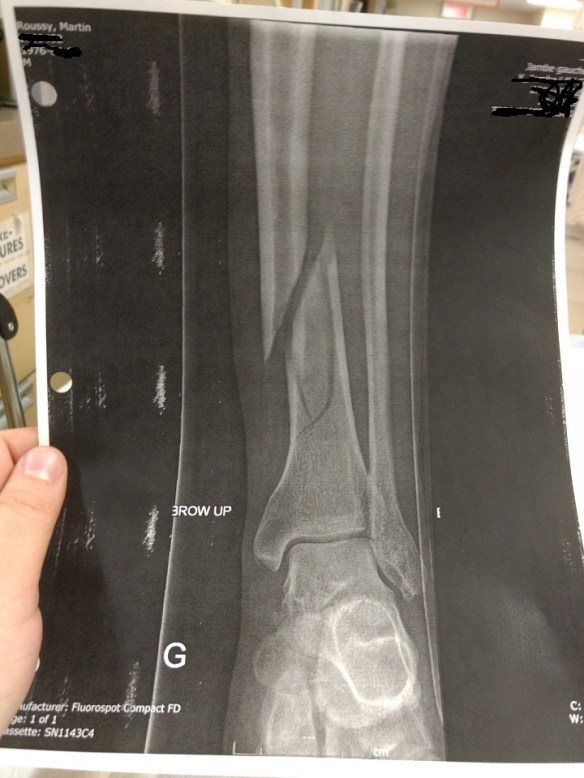

C’est en glissant dans les escaliers que mon pied gauche est resté coincé entre deux marches tandis que mon corps a continué sa chute…

Ça a fait « crack » et mon tibia a fendu en deux!

J’avais le bas de la jambe gauche comme Deadpool qui sacre un coup de pied dans la face de Colossus!

3- Enclouage du tibia! Bref, j’ai maintenant (en plus d’avoir l’attitude de marde) la jambe de Wolverine (le vrai Wolverine là, le petit baveux des BD… Pas Hugh Jackman)!